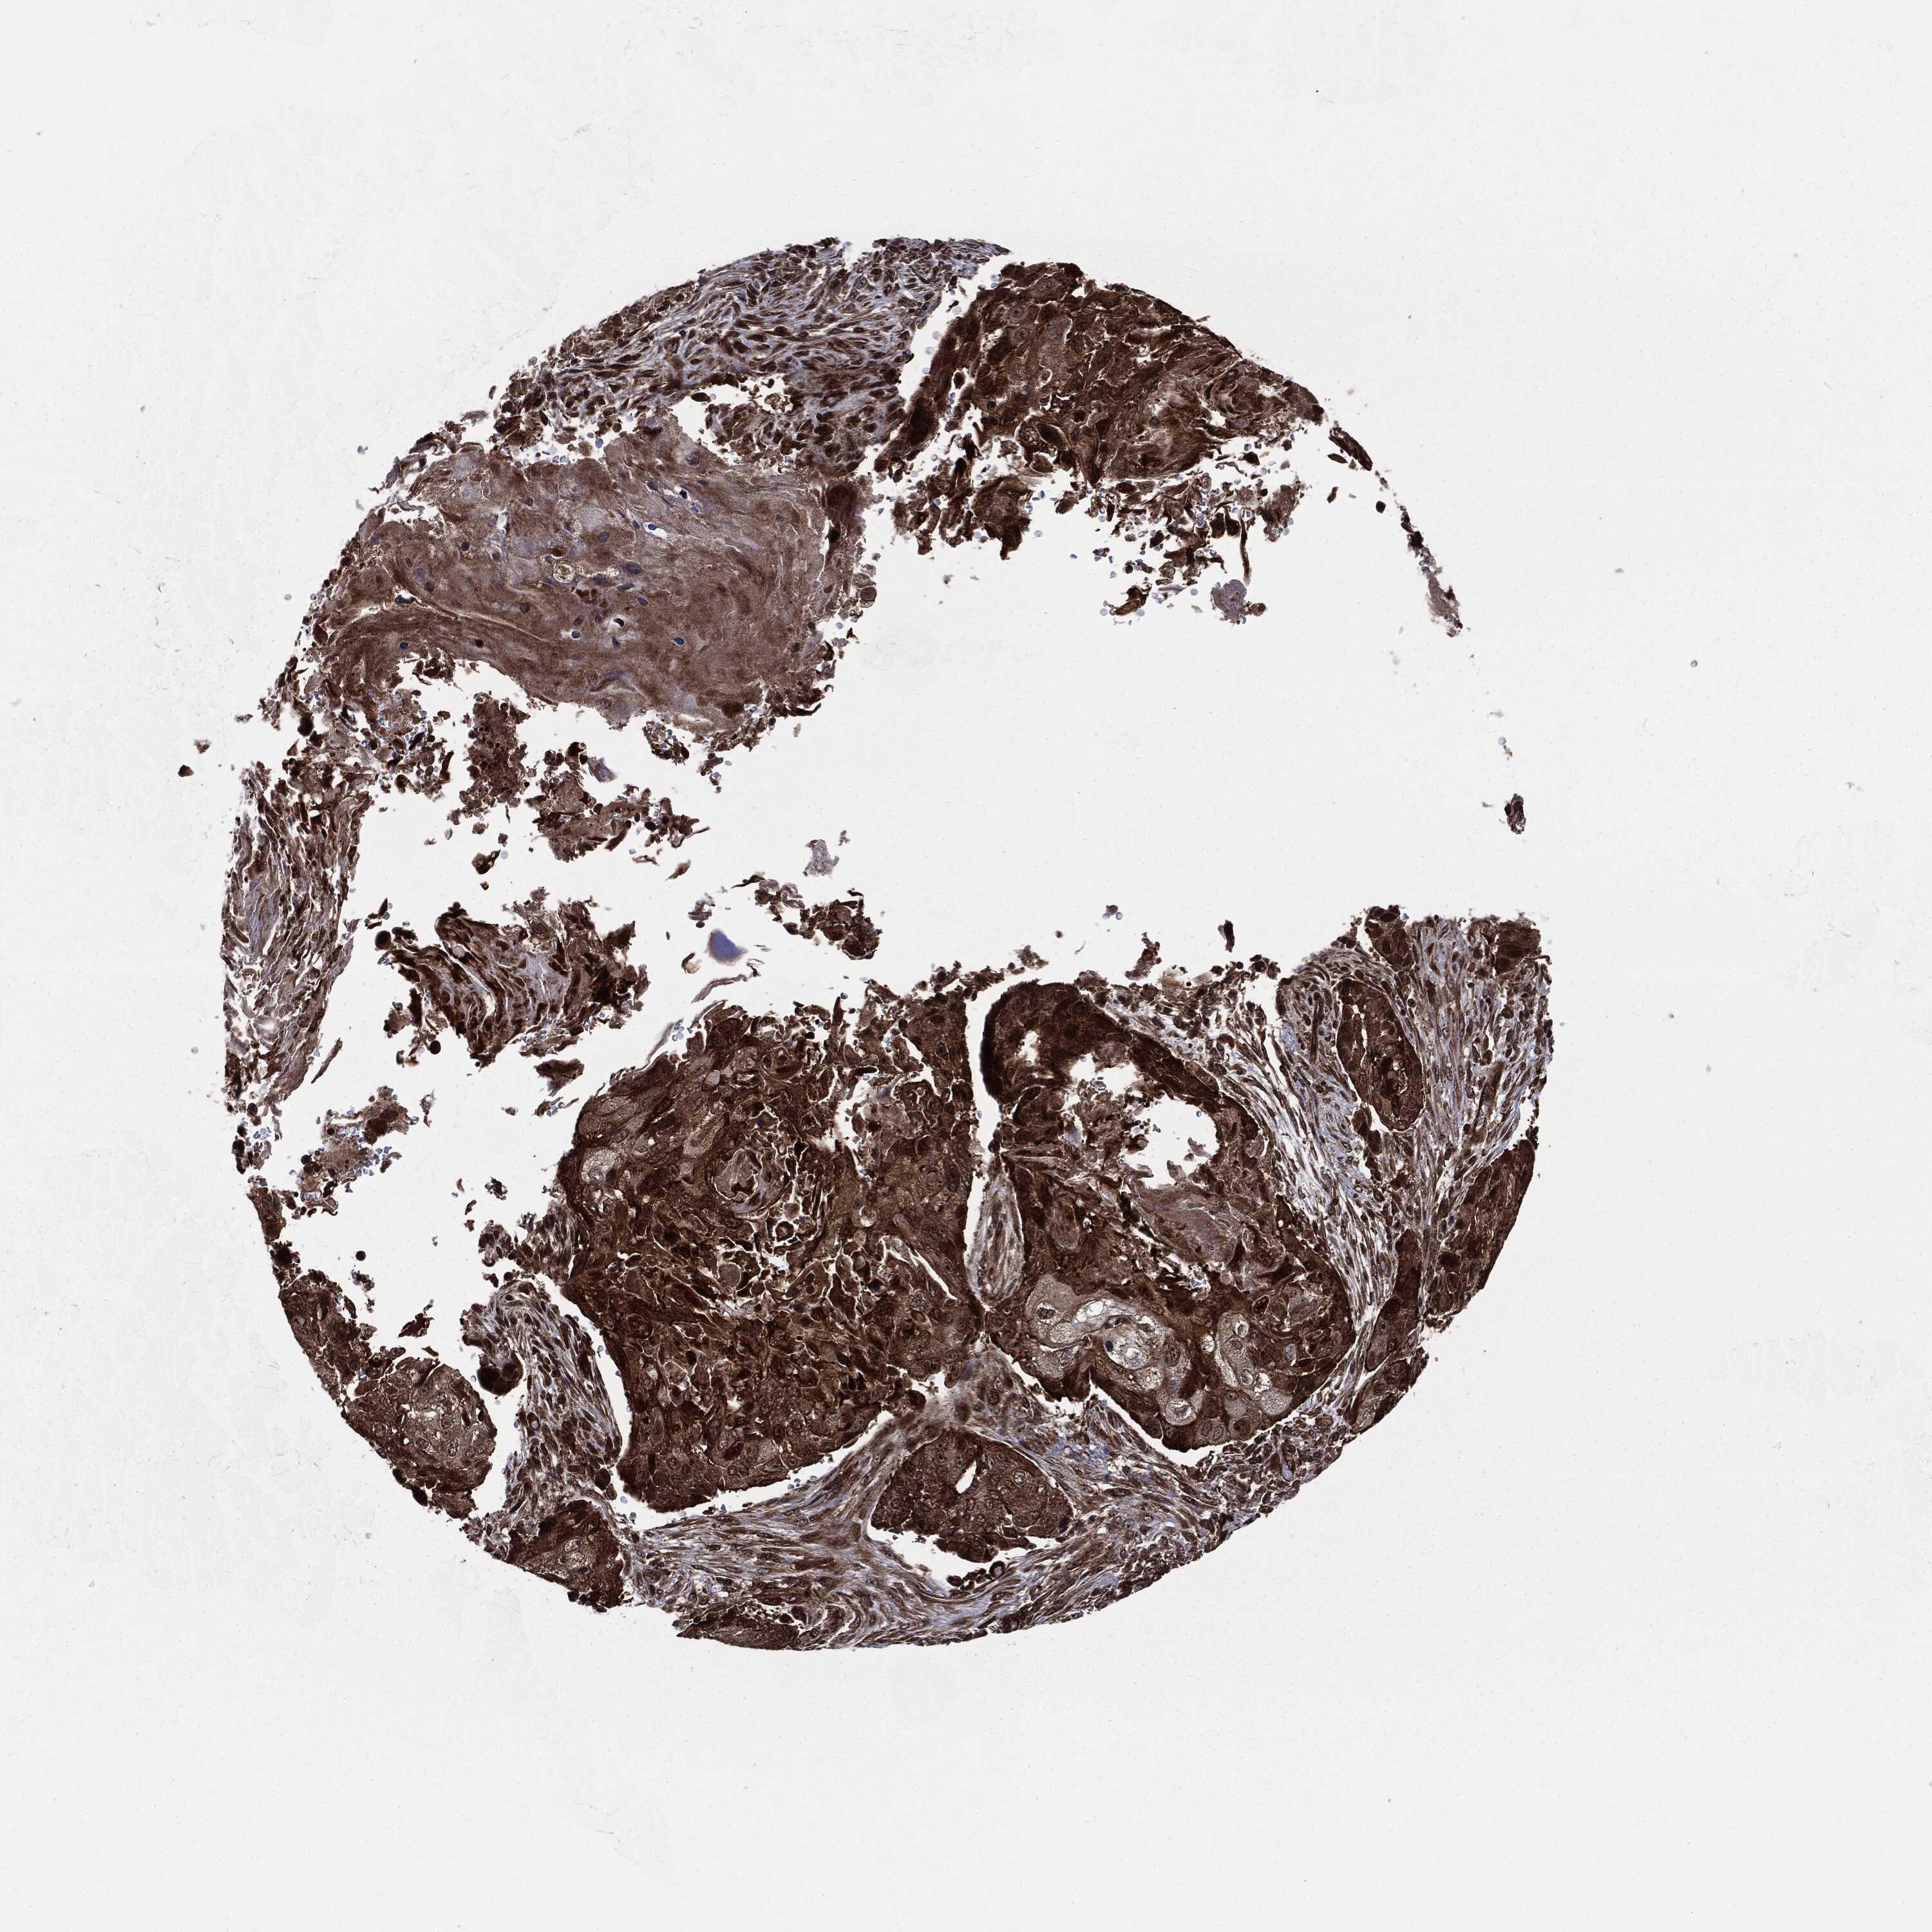

LUNG ADENOCARCINOMA (VALIDATION) - Interactive survival scatter ploti

The Survival Scatter plot shows the clinical status (i.e. dead or alive) for all individuals in the patient cohort, based on the same data that underlies the corresponding Kaplan-Meier plots. Patients that are alive at last time for follow-up are shown in blue and patients who have died during the study are shown in red.

The x-axis shows the expression levels (FPKM) of the investigated gene in the tumor tissue at the time of diagnosis. The y-axis shows the follow-up time after diagnosis (years). Both axes are complimented with kernel density curves demonstrating the data density over the axes. The top density plot shows the expression levels (FPKM) distribution among dead (red) and alive patients (blue). The right density plot shows the data density of the survived years of dead patients with high and low expression levels respectively, stratified using the cutoff indicated by the vertical dashed line through the Survival Scatter plot. This cutoff is automatically defined based on the FPKM cutoff that minimizes the p-score. The cutoff can be changed by dragging the vertical line or by entering a cutoff value in the square labeled "Current cut-off".

Under the Survival Scatter plot the p-score landscape (black curve; left axis) is shown together with dead median separation (red curve; right axis). Dead median separation is the difference in median mRNA expression between patients who have died with high and low expression, respectively. It is calculated as follows: median FPKM expression of dead patients with high expression - median FPKM expression of dead patients with low expression. This is intended to aid the user in visually exploring custom cutoffs and the associated p-scores and dead median separation.

Individual patient data is displayed and can be filtered by clicking on one or more of the category buttons on the top of the page. Categories describing expression level and patient information include: high, low, alive, dead, female, male and tumor stages. The scale of the x-axis can be toggled between linear and log-scale by clicking on the "x log" button. Mouse-over function shows TCGA ID, patient information and mRNA expression (FPKM) for each patient.

& Survival analysisi

Kaplan-Meier plots summarize results from analysis of correlation between mRNA expression level and patient survival. Patients were divided based on level of expression into one of the two groups "low" (under cut off) or "high" (over cut off). X-axis shows time for survival (years) and y-axis shows the probability of survival, where 1.0 corresponds to 100 percent.

CARD6 is not prognostic in Lung Adenocarcinoma (validation)

Best expression cut offi

Based on the FPKM value of each gene, patients were classified into two groups and association between prognosis (survival) and gene expression (FPKM) was examined. The best expression cut-off refers the FPKM value that yields maximal difference with regard to survival between the two groups at the lowest log-rank P-value. Best expression cut-off was selected based on survival analysis .

When clicking on this number, the vertical dashed line indicating cut-off, the interactive survival plot, and the Kaplan-Meier curve will be adjusted to show results based on the best expression cut-off.

: 14.32

Median expressioni

Median expression refers to the median FPKM value calculated based on the gene expression (FPKM) data from all patients in this dataset. When clicking on this number, the vertical dashed line indicating cut-off, the interactive survival plot, and the Kaplan-Meier curve will be adjusted to show results based on the median expression.

: N/A

Median follow up timei

Median follow up time refers to the median time (years) after diagnosis with this type of cancer, based on clinical data from all patients in this dataset.

P scorei

Log-rank P value for Kaplan-Meier plot showing results from analysis of correlation between mRNA expression level and patient survival.

N/A

5-year survival highi

5-year survival for patients with higher expression than the expression cutoff.

For melanoma and glioma, 3-year survival is shown.

5-year survival lowi

5-year survival for patients with lower expression than the expression cutoff.

TCGA RNA samplesi

RNA-seq data is reported as average FPKM (number Fragments Per Kilobase of exon per Million reads), generated by the The Cancer Genome Atlas (TCGA) .

Normal distribution across the dataset is visualized with box plots, shown as median and 25th and 75th percentiles. Points are displayed as outliers if they are above or below 1.5 times the interquartile range. FPKM values of the individual samples are presented next to the box plot.

Average pTPM 11.2

Number of samples 105